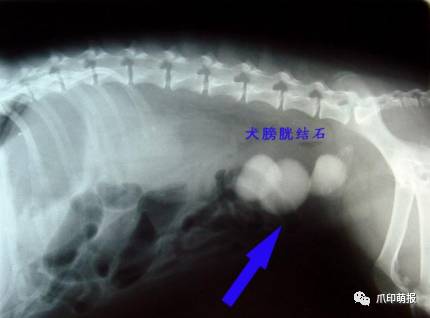

引起尿道阻塞的原因有感染、发炎、结石、肿瘤等原因,如果是部份阻塞,当膀胱内尿液的压力大于阻力时,尿液及会不自主的流出,引起尿*禁失**。

膀胱是储存尿液的位置,在膀胱发炎或结石的时候,因为膀胱壁的过度刺激,引起膀胱平滑肌的收缩,造成不定期的排尿,也可能是因为膀胱内壁有肿瘤的生长,引起尿液储存量下降,而引起排尿频率上升。